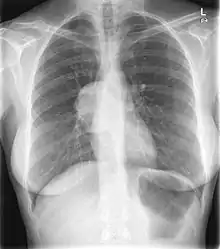

About 80% of pleural SFTs originate in the visceral pleura, while 20% arise from parietal pleura.[5] Although they are often very large tumors (up to 40 cm. in diameter), over half are asymptomatic at diagnosis.[5] While some researchers have proposed that a SFT occupying at least 40% of the affected hemithorax be considered a "giant solitary fibrous tumor",[6] no such "giant" variant has yet been recognized within the most widely used pleural tumor classification scheme.[1]